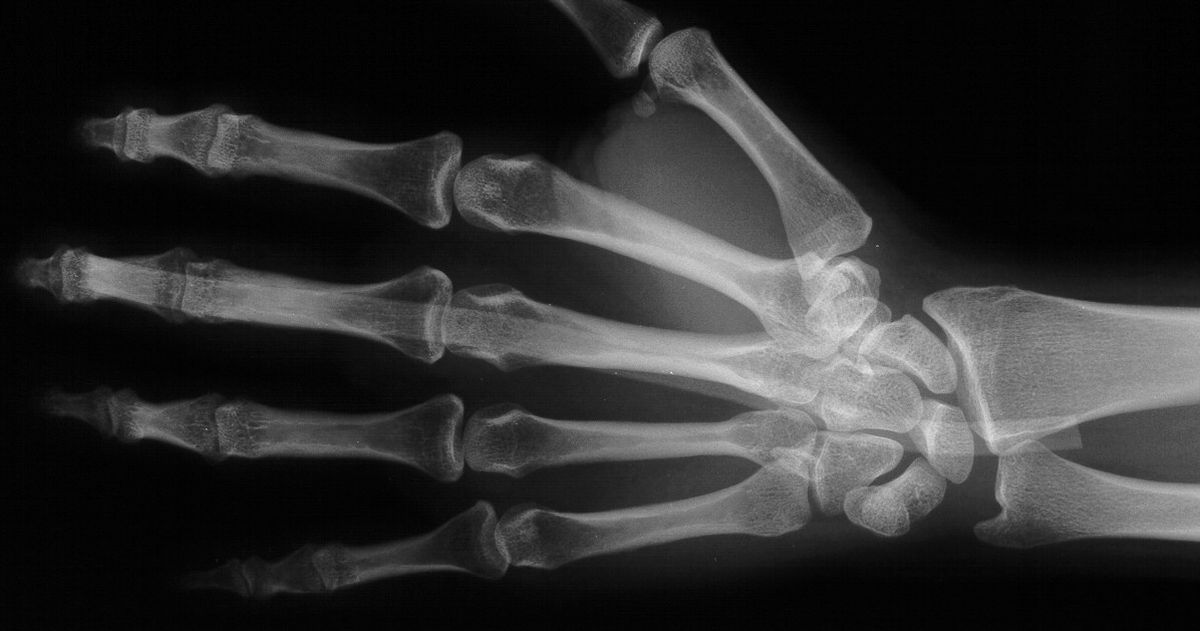

Radiographs demonstrating proper tendon spacer position and no bowstringing.